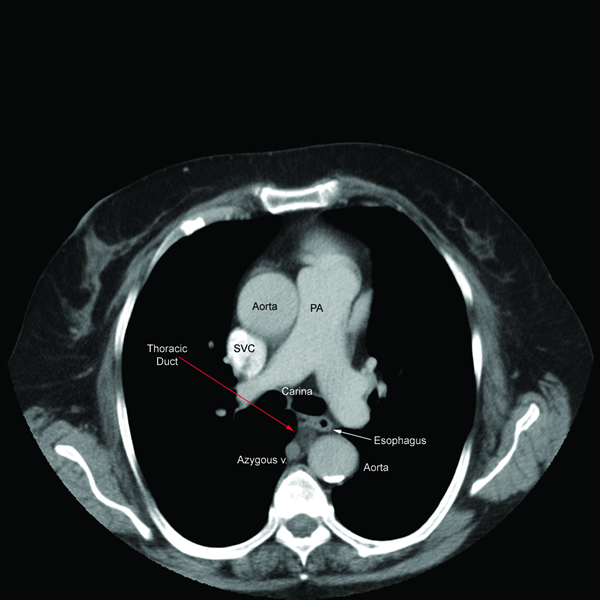

Thoracic ct scan anatomy